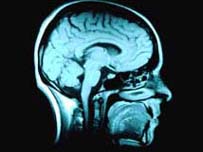

O estudo incluiu mapeamento do cérebro e testes psicológicos de 200 jovens

Para investigar a razão de algumas pessoas desenvolverem o problema e outras não, os pesquisadores entrevistaram os voluntários, mapearam seu cérebro, submeteram-nos a testes psicológicos e análises genéticas.

Exames de mapeamento do cérebro também revelaram que os jovens participantes da pesquisa que eram portadores da variante do gene têm maior probabilidade de mostrar atividade cerebral anormal nas regiões frontal e temporal - áreas freqüentemente associadas à esquizofrenia.